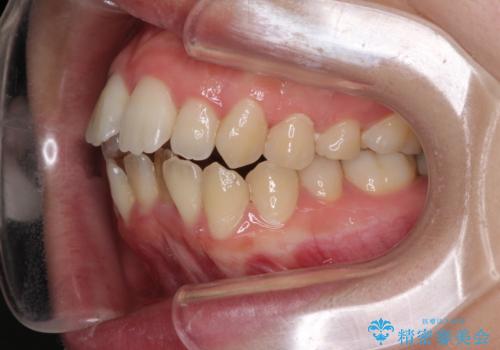

Eラインを改善したい ハーフリンガルによる抜歯矯正

- 口元の突出感を気にして来院された患者様です。

上下左右の第一小臼歯4本を抜歯して口元を下げる治療計画としました。

舌の突出癖が強く、口元を引っ込める力に拮抗してしまい、抜歯スペースを閉じるまでに時間がかかりました。

また途中出産もありましたが、無事に治療を終えることができました。